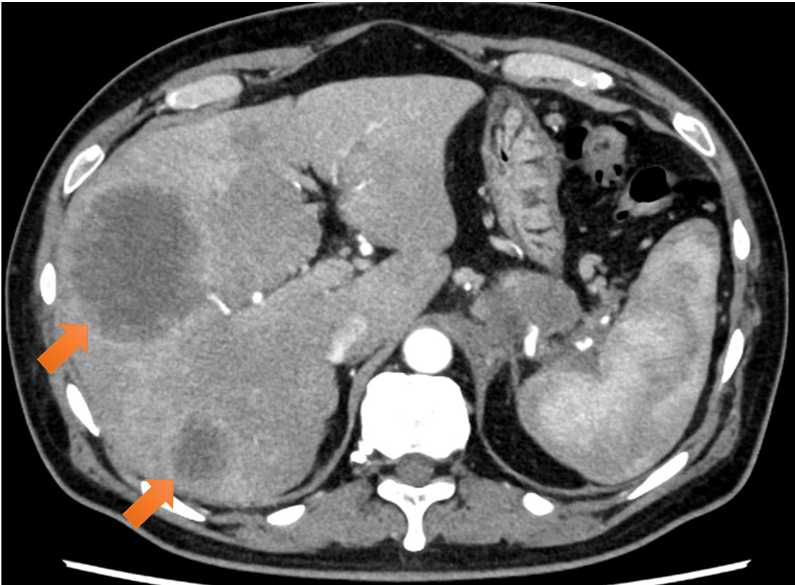

図4.多発肝転移

肝両葉に75mm大までのリング状濃染を伴う腫瘤を多数認めた。